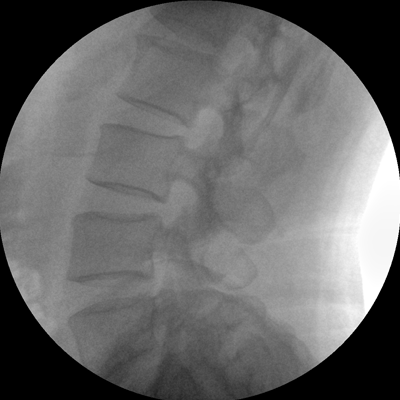

小巧輕便 超凡靈動 PLX116

●一體化機(jī)架設(shè)計,占地空間小,移動靈活

●一人獨立操作,即可完成C形臂的移動與曝光

●全數(shù)字化百萬像素影像系統(tǒng),圖像清晰

●多種工作模式任意選擇,滿足多種臨床需求